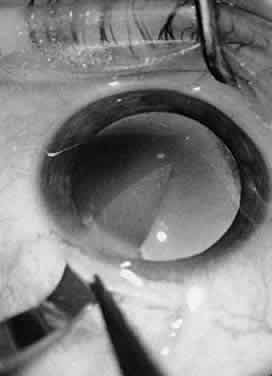

Iris tissue is extremely delicate, and it should be handled with great care. A Bonn 0.12-mm forceps is best used for handling iris tissue, although the iris should be grasped only when it is being incised or sutured. When a peripheral iridectomy is made, the iris may be grasped with a Bonn 0.12-mm fixation forceps or a smooth forceps. With gentle traction, the iris may be pulled through the surgical incision and then incised with Vannas scissors (Fig. 41). The iris then may be repositioned with a viscoelastic substance or a spatula, if necessary. If the iris must be sutured, Bonn forceps or smooth forceps should be used, as should a blood vessel round needle, which does not have a cutting edge and will thus avoid unnecessary tearing of the iris stroma.

Fig. 41. The iris is pulled through a limbal incision with a 0.12-mm fixation forceps and incised with Dewecker's scissors. In this way, a peripheral iridectomy is performed.